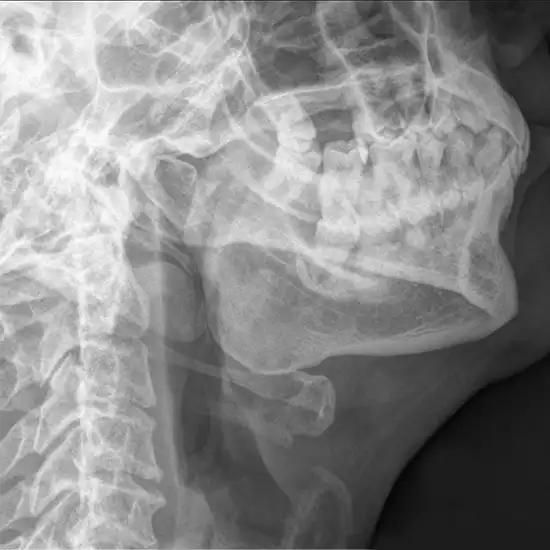

X-RAY MANDIBLE LATERAL OBLIQUE VIEW (R/L) PROCEDURE

X-ray mandible lateral oblique view is used to show the displacement fracture of the affected side mandible.

This view is useful in assessing:

•             Fracture right or left side mandible

•             Neoplastic changes

•             Inflammatory processes

•             Body of mandibleto

•             To see the molar and premolar jaw

Part positioning

• The patient is positioned next to Bucky, who is standing or sitting.

• Put your head in a lateral position and lean your interested side against the IR.

• The patient must have his or her mouth and teeth as near together as possible.

• Head is in true lateral position and then 45-degree rotation demonstrates mentum.